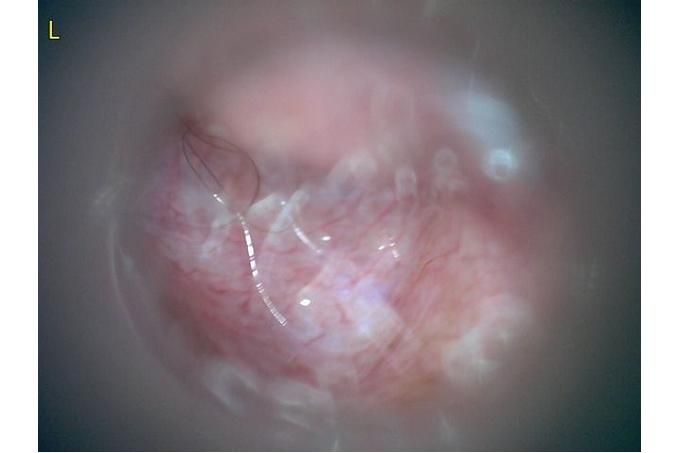

사진만 보고 확진할 수는 없지만 지금 올려주신 귀는 적어도 오른쪽은 정상으로 보이기 어렵습니다 왼쪽은 비교적 연분홍에 가까워 보이지만 오른쪽은 털과 분비물이 많이 차 있고 피부가 자극받은 듯한 모습이라 외이염 가능성을 먼저 생각하게 됩니다 그리고 질문자님이 적어주신 머리 털기 하루 여러 번 귀 만질 때 통증 솜만 닿아도 예민함 귀 긁기 같은 증상은 외이염에서 흔한 신호입니다

제 판단을 정리하면 지금 상태는 오른쪽 외이염 가능성이 높고 집에서는 알코올 세정제와 강한 귀세정은 잠시 멈추는 쪽이 더 안전합니다 그리고 약을 쓴다면 아무 귀약이 아니라 고막 확인과 세포검사 결과에 맞는 약이 필요합니다 질문자님처럼 이미 여러 말을 들어 혼란스러운 경우에는 기준을 하나로 잡으셔야 합니다 귀가 아픈 날에는 세정부터 하지 말고 먼저 통증과 염증을 가라앉힌 뒤 필요하면 부드럽게 청소하는 순서가 더 맞는 경우가 많습니다 하품은 귀 통증과 턱 주변 불편 때문에 같이 늘 수 있습니다

제가 드리고 싶은 한마디는 이겁니다 지금 귀는 아무것도 안 해도 되는 귀처럼 보이지는 않지만 집에서 이것저것 바꿔 넣어볼 귀도 아닙니다 오른쪽은 외이도 염증과 통증 쪽으로 보고 자극적인 세정은 피하면서 원인 확인 후 한 가지 치료로 정리하는 쪽이 맞아 보입니다